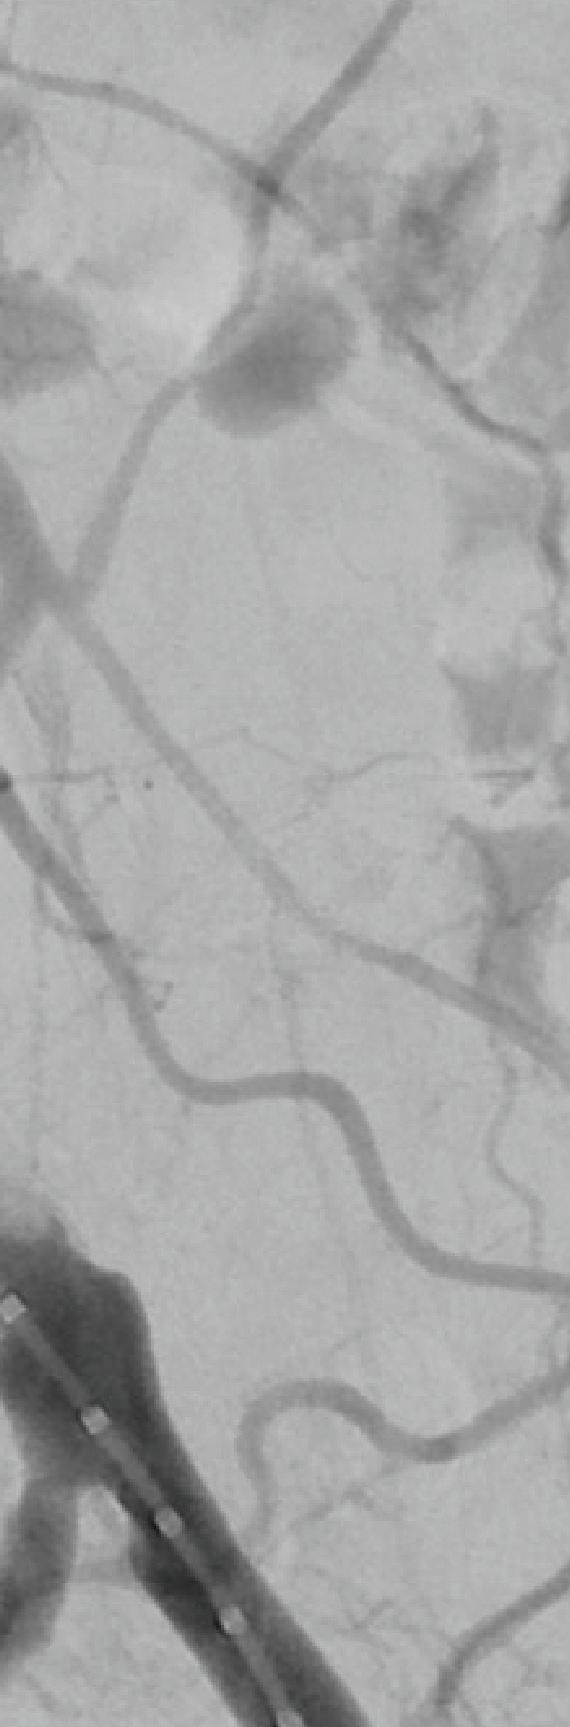

THE SAFE MANAGEMENT OF AORTOiliac graft infections has proven possible by utilizing either cryopreserved arterial allografts (CAA) or rifampin-soaked Dacron (RSD) for select in-situ reconstruction based on the findings of a recent study conducted by the Mayo Clinic and Karolinska Institutet.

Tabiei et al’s objective was to compare the safety and effectiveness of CAA and RSD as options for in-situ reconstruction in aorto-iliac graft-infected patients.

Data collected from aortic and iliac graft-infected patients undergoing in-situ reconstruction with either CAA or RSD from January 2002 through August 2022 were analyzed retrospectively to assess overall survival rates as well as secondary outcomes such as graft-related intervention, reinfection, perioperative mortality, and major morbidity,

While it was found that reinfection rates among the RSD group were lower compared to the CAA group, it was not statistically significant, making both interventions viable options for infected patients.

Although a single-center retrospective cohort study, said Tabiei, results showed “comparable early and long-term morbidity and mortality between the groups.”

VISCERAL ARTERIES PRIORITIZING

The study included 149 subjects, 80 of which received RSD intervention and 60 who underwent CAA, with a mean age of 68.9 and 69.1, respectively. Moreover, endovascular stent grafts were infected in 60 patients, 41 of which were in the CAA group, with the remaining 19 patients in the RSD group.

With respect to graft-enteric fistulas, they were significantly more common in the RSD group, and management included complete resection of the infected graft. Aortic reconstructions were covered in omentum in 57 CAA patients and 63 patients in the RSD group.

There was a median follow-up of 20.5 months in the CAA group and 21.5 months in the RSD group, with

overall survival at five years similar between the two cohorts, with 59.2% in the RSD group and 59% in the CAA group. Freedom from graft-related reintervention at one and five years was 81.3% and 66.2% in CAA patients compared to 95.6% and 92.5% in RSD patients.

Tabiei went on to describe that indications for reintervention in the CAA group included five patients with stenosis, four with pseudoaneurysm, two occlusion patients, one with graft-limb kinking, and one patient who experienced rupture.

Keith Calligaro, MD, Philadelphia: “I applaud your effort but I don’t know if we’re ever going to get a good answer on this—it’s all retrospective … I personally take a different attitude about the use of cryograft. When it's a younger patient, I tend to use the cryograft because I'm more worried about recurrent infection, but every series has shown that cryograft is more likely to develop recurrent stenosis. That's the advantage of rifampin—you're less likely to get recurrent infection.”

In the RSD group, indications for reintervention included three patients with reinfection, one occlusion patient, one endoleak patient, one with omental coverage, and one incidence of rupture. Freedom from reinfection at one and five years was 98.3% and 94.9% in the CAA cohort compared to 92.5% and 87.2% for the RSD group.

Wrapping up, Tabiei concluded that the study found both CAA and RSD to be suitable interventions, but noted that reintervention was more common with CAA—ultimately reaffirming that individualized treatment and long-term follow-up are most appropriate with aortic and iliac graft-infected patients.

Tabiei added that at his institution, CAA are considered in older patients, and in cases of highly virulent microorganisms and such instances as intra-abdominal abscesses. RSD tends to be used in younger patients and in urgent cases.